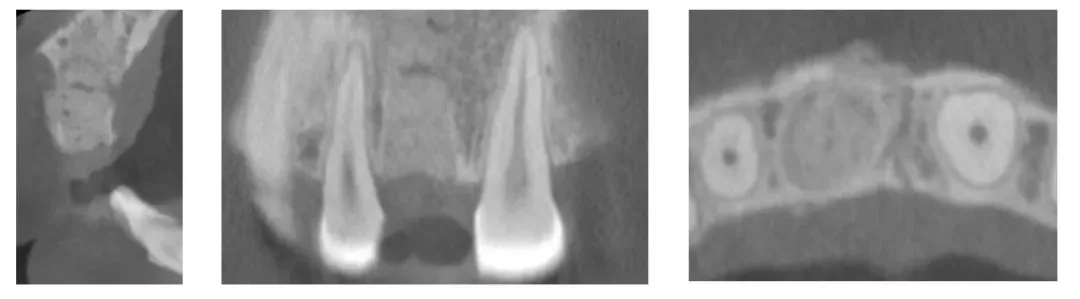

·      GBR半年后复查CBCT,显示垂直及水平向骨量充足,骨弓轮廓基本无塌陷。

垂直、水平向骨量充足(备注:影像上的修复体信息为口内参照邻牙修改后的理想临时修复体)

颊侧水平向骨弓轮廓基本无塌陷,维持较好的牙根形态

·      参照邻牙,在原临时牙上修改形态及调整咬合后拍摄CBCT获取修复体及骨信息。取下临时修复体口扫获取软组织信息,拟合软硬组织及修复体信息设计种植方案。